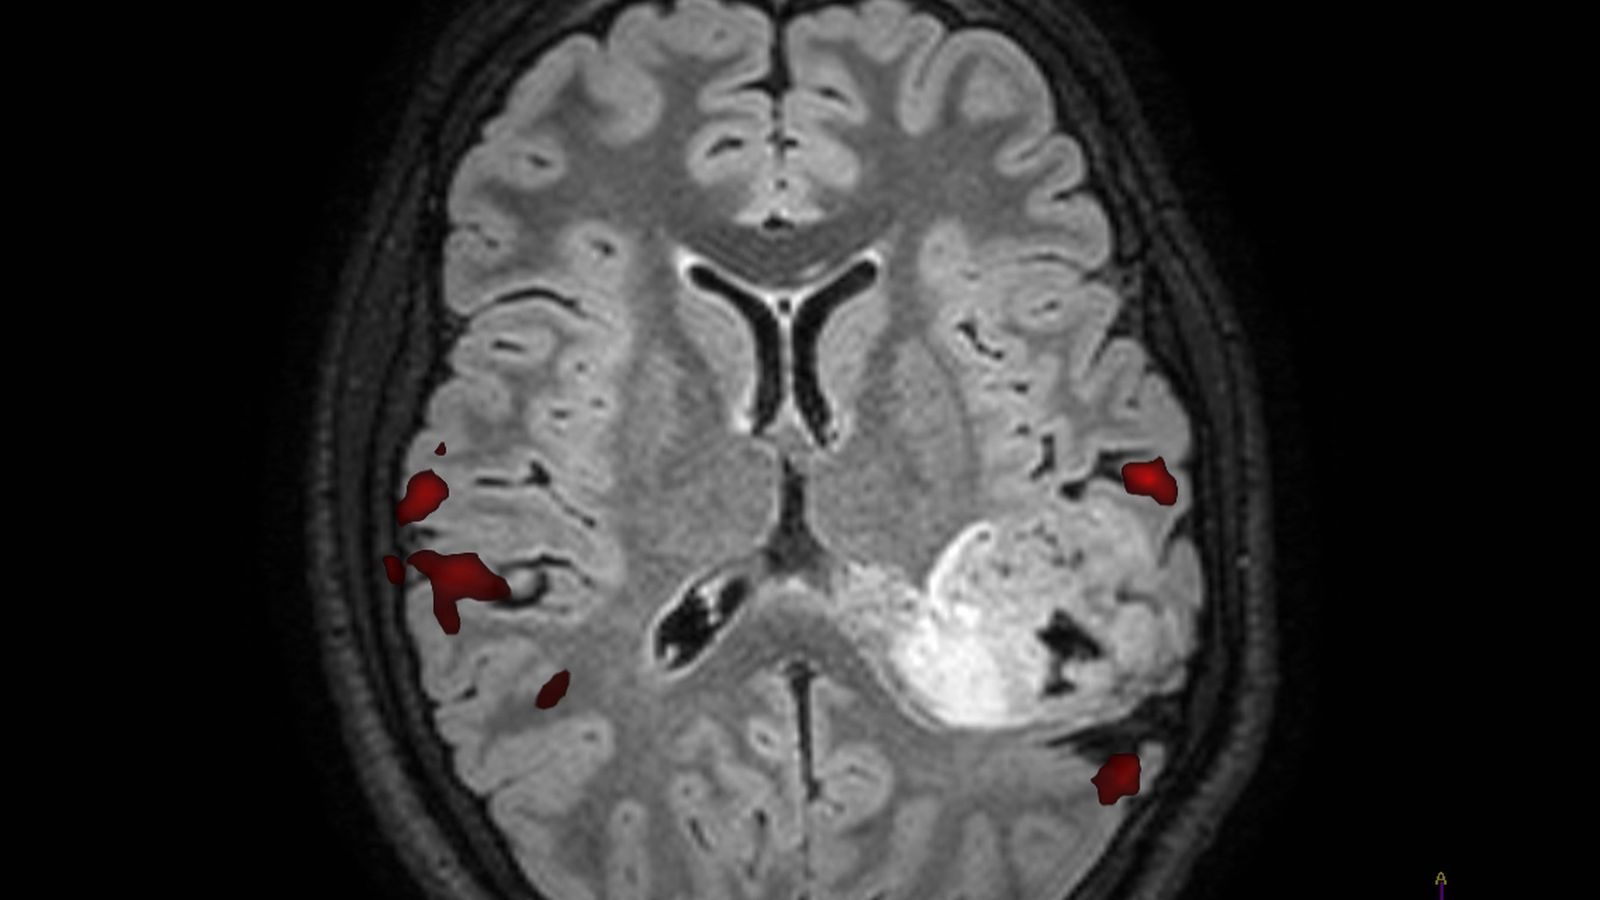

En las zonas rojas se aprecia las áreas del lenguaje. En la blanca, el tumor.

En las zonas rojas se aprecia las áreas del lenguaje. En la blanca, el tumor. / M. H.